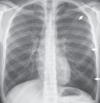

Atelectasia pasiva en el neumotórax. Una radiografía posteroanterior de tórax muestra un neumotórax moderado del lado izquierdo y una pequeña cantidad de líquido pleural izquierdo, lo que resulta en un nivel de líquido en el surco costofrénico izquierdo. El neumotórax se puede reconocer al observar el margen de la pleura visceral (flechas). Aunque el volumen del pulmón izquierdo ha disminuido, no hay un aumento aparente en la opacidad del pulmón izquierdo.